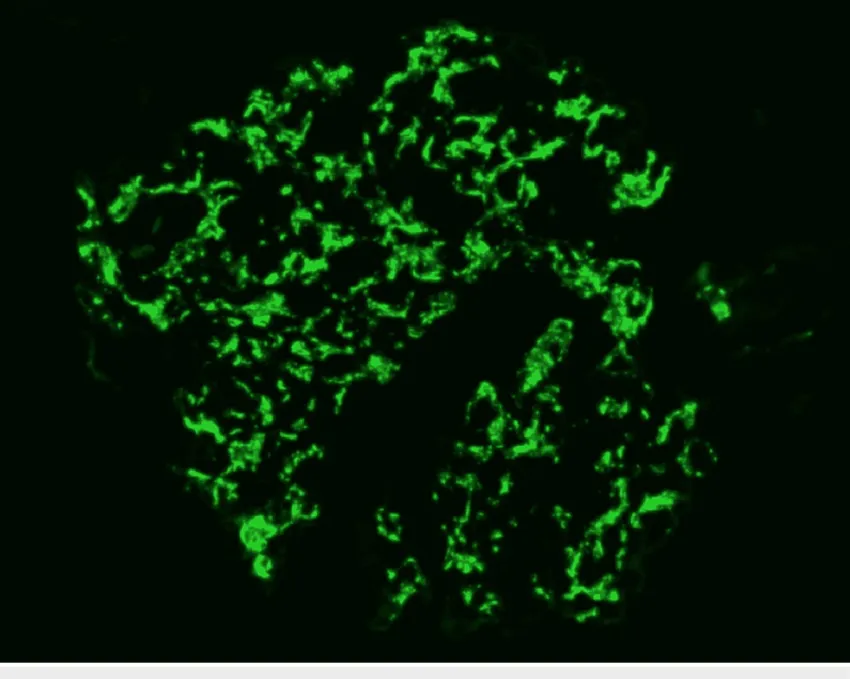

DRC “indeterminada” raramente é falta de diagnóstico — quase sempre é falta de método. Tempo de evolução, urina bem avaliada, USG renal e história clínica dirigida mudam conduta e evitam erros comuns na prática nefrológica.